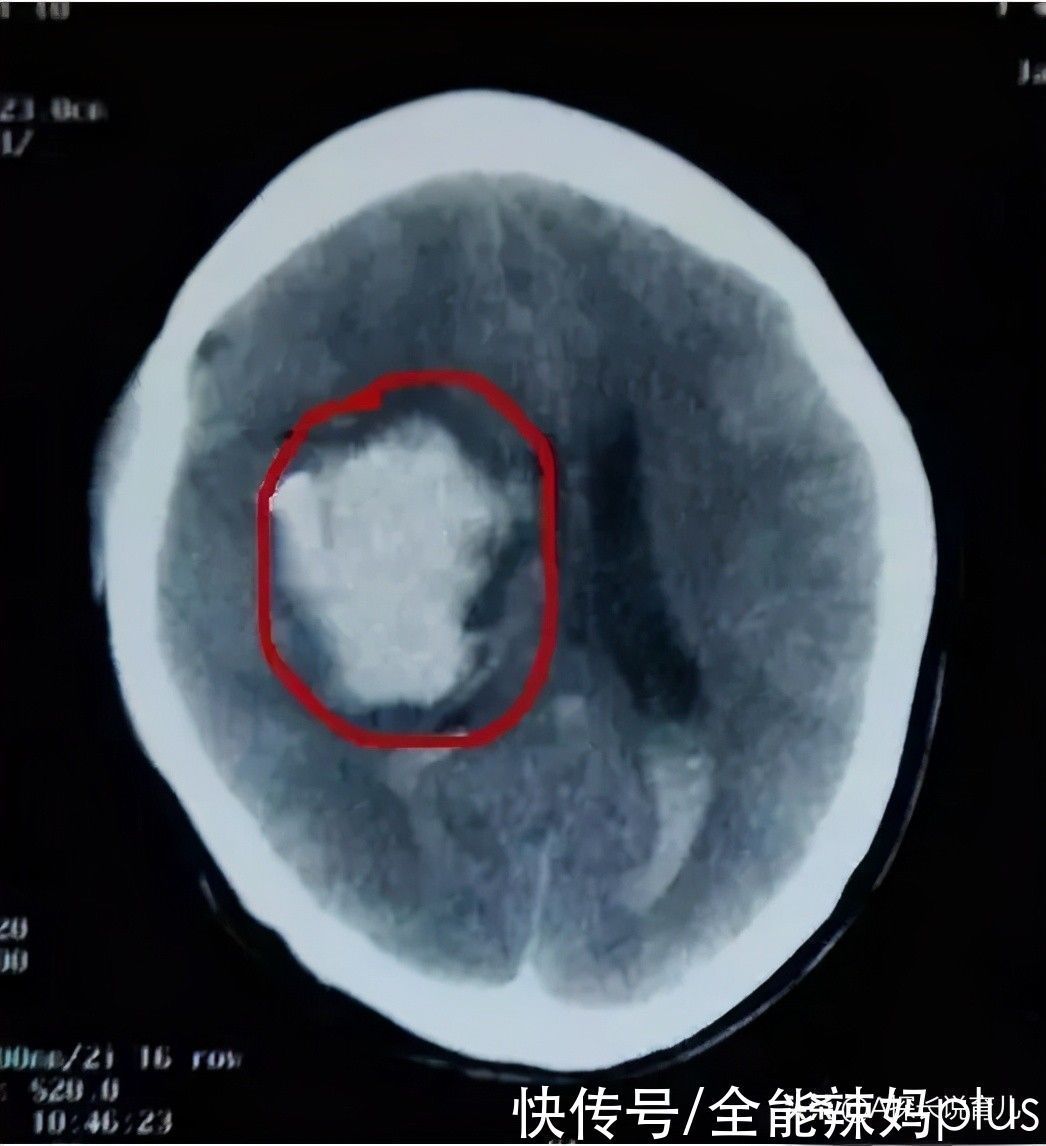

如若是关乎到孩子的脑颅内神经以及其他一些比较关键的部位的话,那也一定要及时就医,避免耽误了治疗。